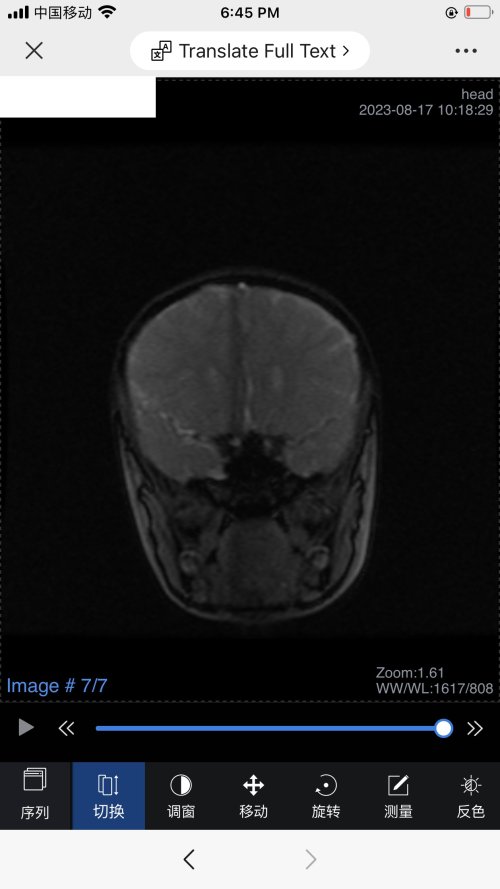

反馈下情况,孩子在国内的医院已经进行过一轮全面检测,没发现什么问题,但是现象是存在的。医生也没什么办法。医生说核磁共振和脑电图没问题,我们也不是很看得懂,各位如果懂的,请指点一下。另外进行了部分基因检测,没发现异常。下一步,我们国庆后打算去更权威的医院去碰碰运气。谢谢各位!

513.6 KB 查看: 103

532.8 KB 查看: 142

551 KB 查看: 132

526.8 KB 查看: 133

510 KB 查看: 103

506.4 KB 查看: 124

495.7 KB 查看: 165